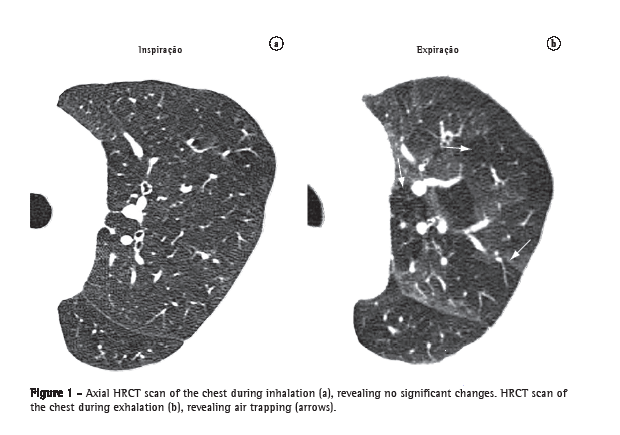

Lymph node enlargement (linfonodomegalia)

Lymph node enlargement is characterized by the increase in volume in one or more lymph nodes, due to any cause, surpassing the dimensional limits considered normal for the lymph node chain in question (Figure 31).(52,53) The term "adenomegaly" is not an acceptable synonym, since lymph nodes are not true glandular structures. The term "linfonodopatia" ("lymphatic disease") is reserved for situations in which a disease, such as necrosis, has been identified within a lymph node.